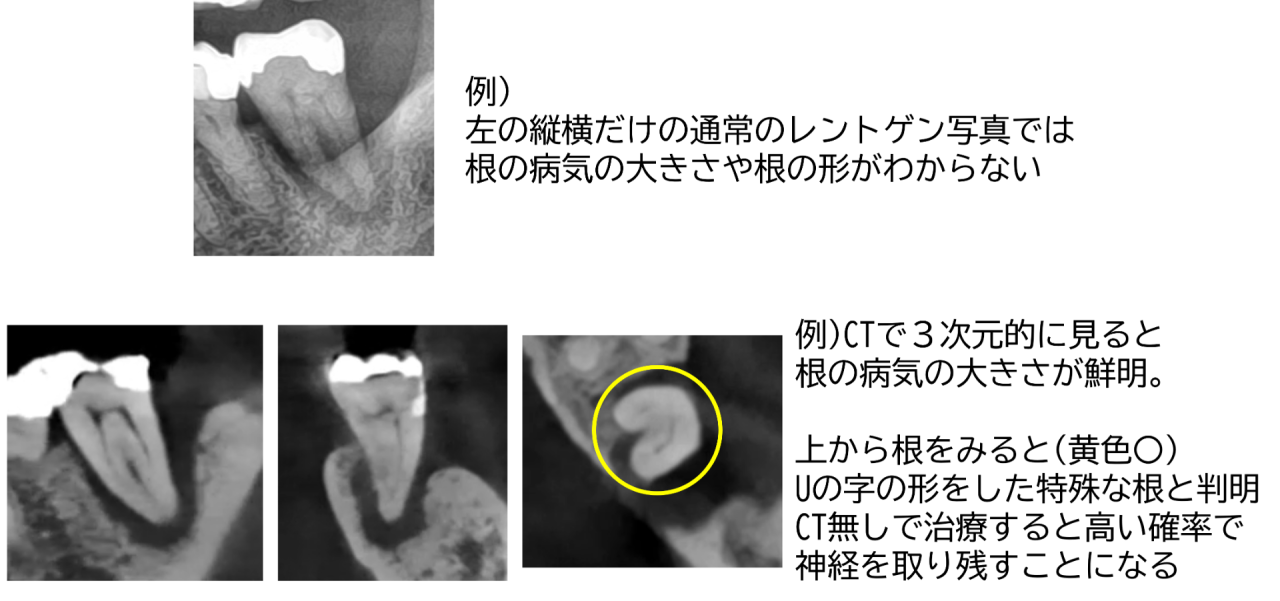

保険治療では、基本的にはCTは撮れません。縦横だけのレントゲンで行うことがほとんどです。

根管治療を成功させるには、CTも必須になります。縦横、そして奥行きの3次元が見えないと、その歯の情報が全くわかりません。

分からない状態でぶっつけ本番で根管治療を行っても、治療の成功率は当然低いため行わない方がよいです。

当院ではCTであらかじめ根を全て精密に検査できるため、治療の計画を綿密に立てて行い成功率が高まります。